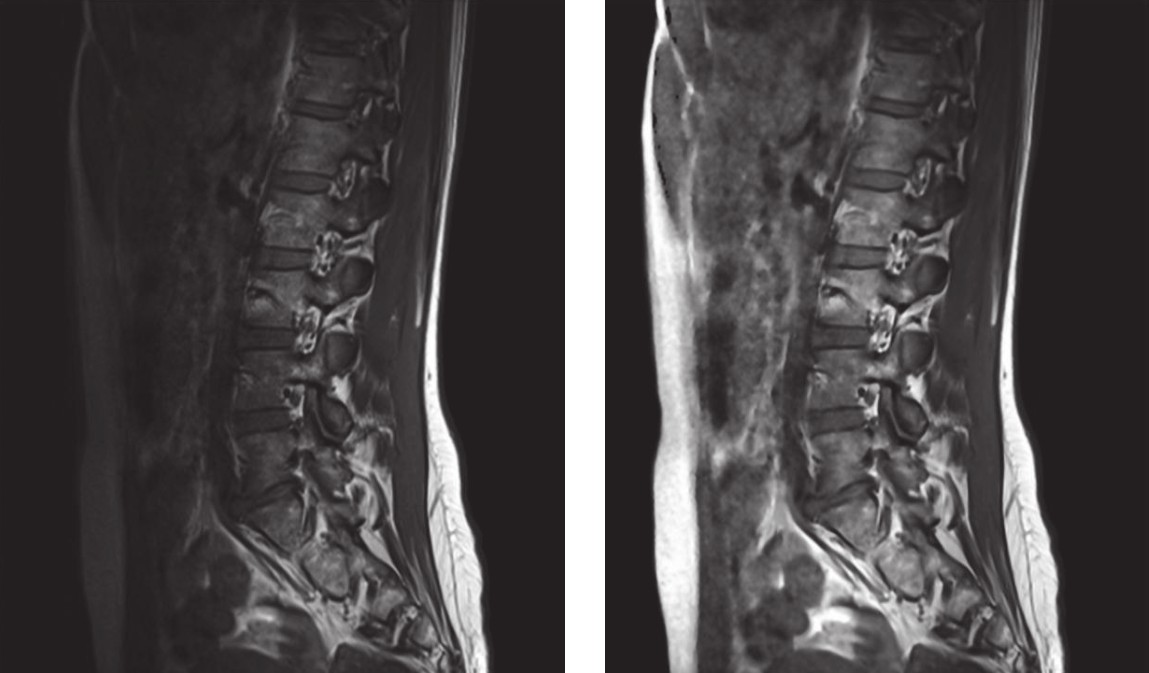

Magnetic resonance imaging (MRI) is the gold standard for visualization of vertebral column disease, providing reliable images of the vertebral column with high-quality soft tissue visualization. MRI is suitable for almost all vertebral column disorders, but noninvasive observations provide only limited data support. Additive manufacturing provides new possibilities for constructing scaffold models with biophysical properties, but a reasonable model requires the assistance of complex scanning data and computational models. Animal models are also commonly used vertebral column research tools, but small animals are usually unable to perform effective vertebral column drug delivery, large animals face higher costs and ethical issues, and most of the compounds that are feasible in animal experiments fail in the stage of clinical translation.

1. Gawel, D.; et al. Automatic spine tissue segmentation from MRI data based on cascade of boosted classifiers and active appearance model. Biomed Research International. 2018, 10: 1155. Distributed under CC BY 4.0, without modification.